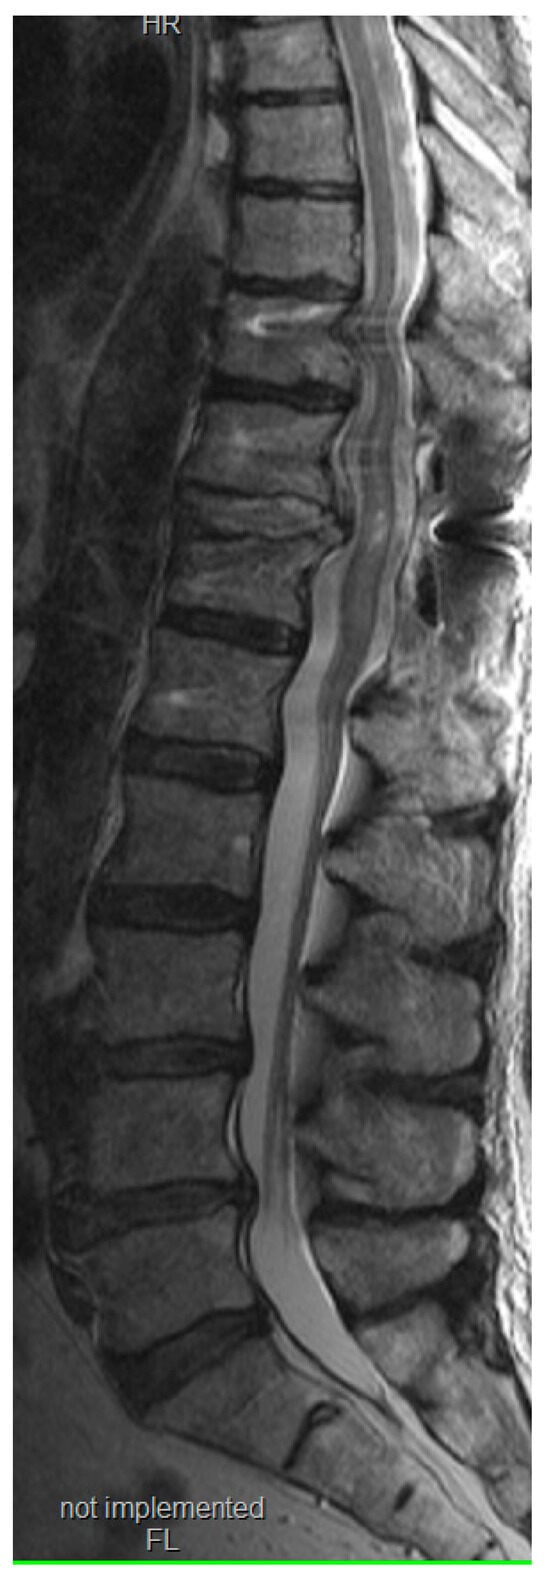

Figure 8.

Postoperative T2 weighted magnetic resonance image revealing adequate decompression. Despite the slight artifacts from the screws, the medullary contusion is visible.